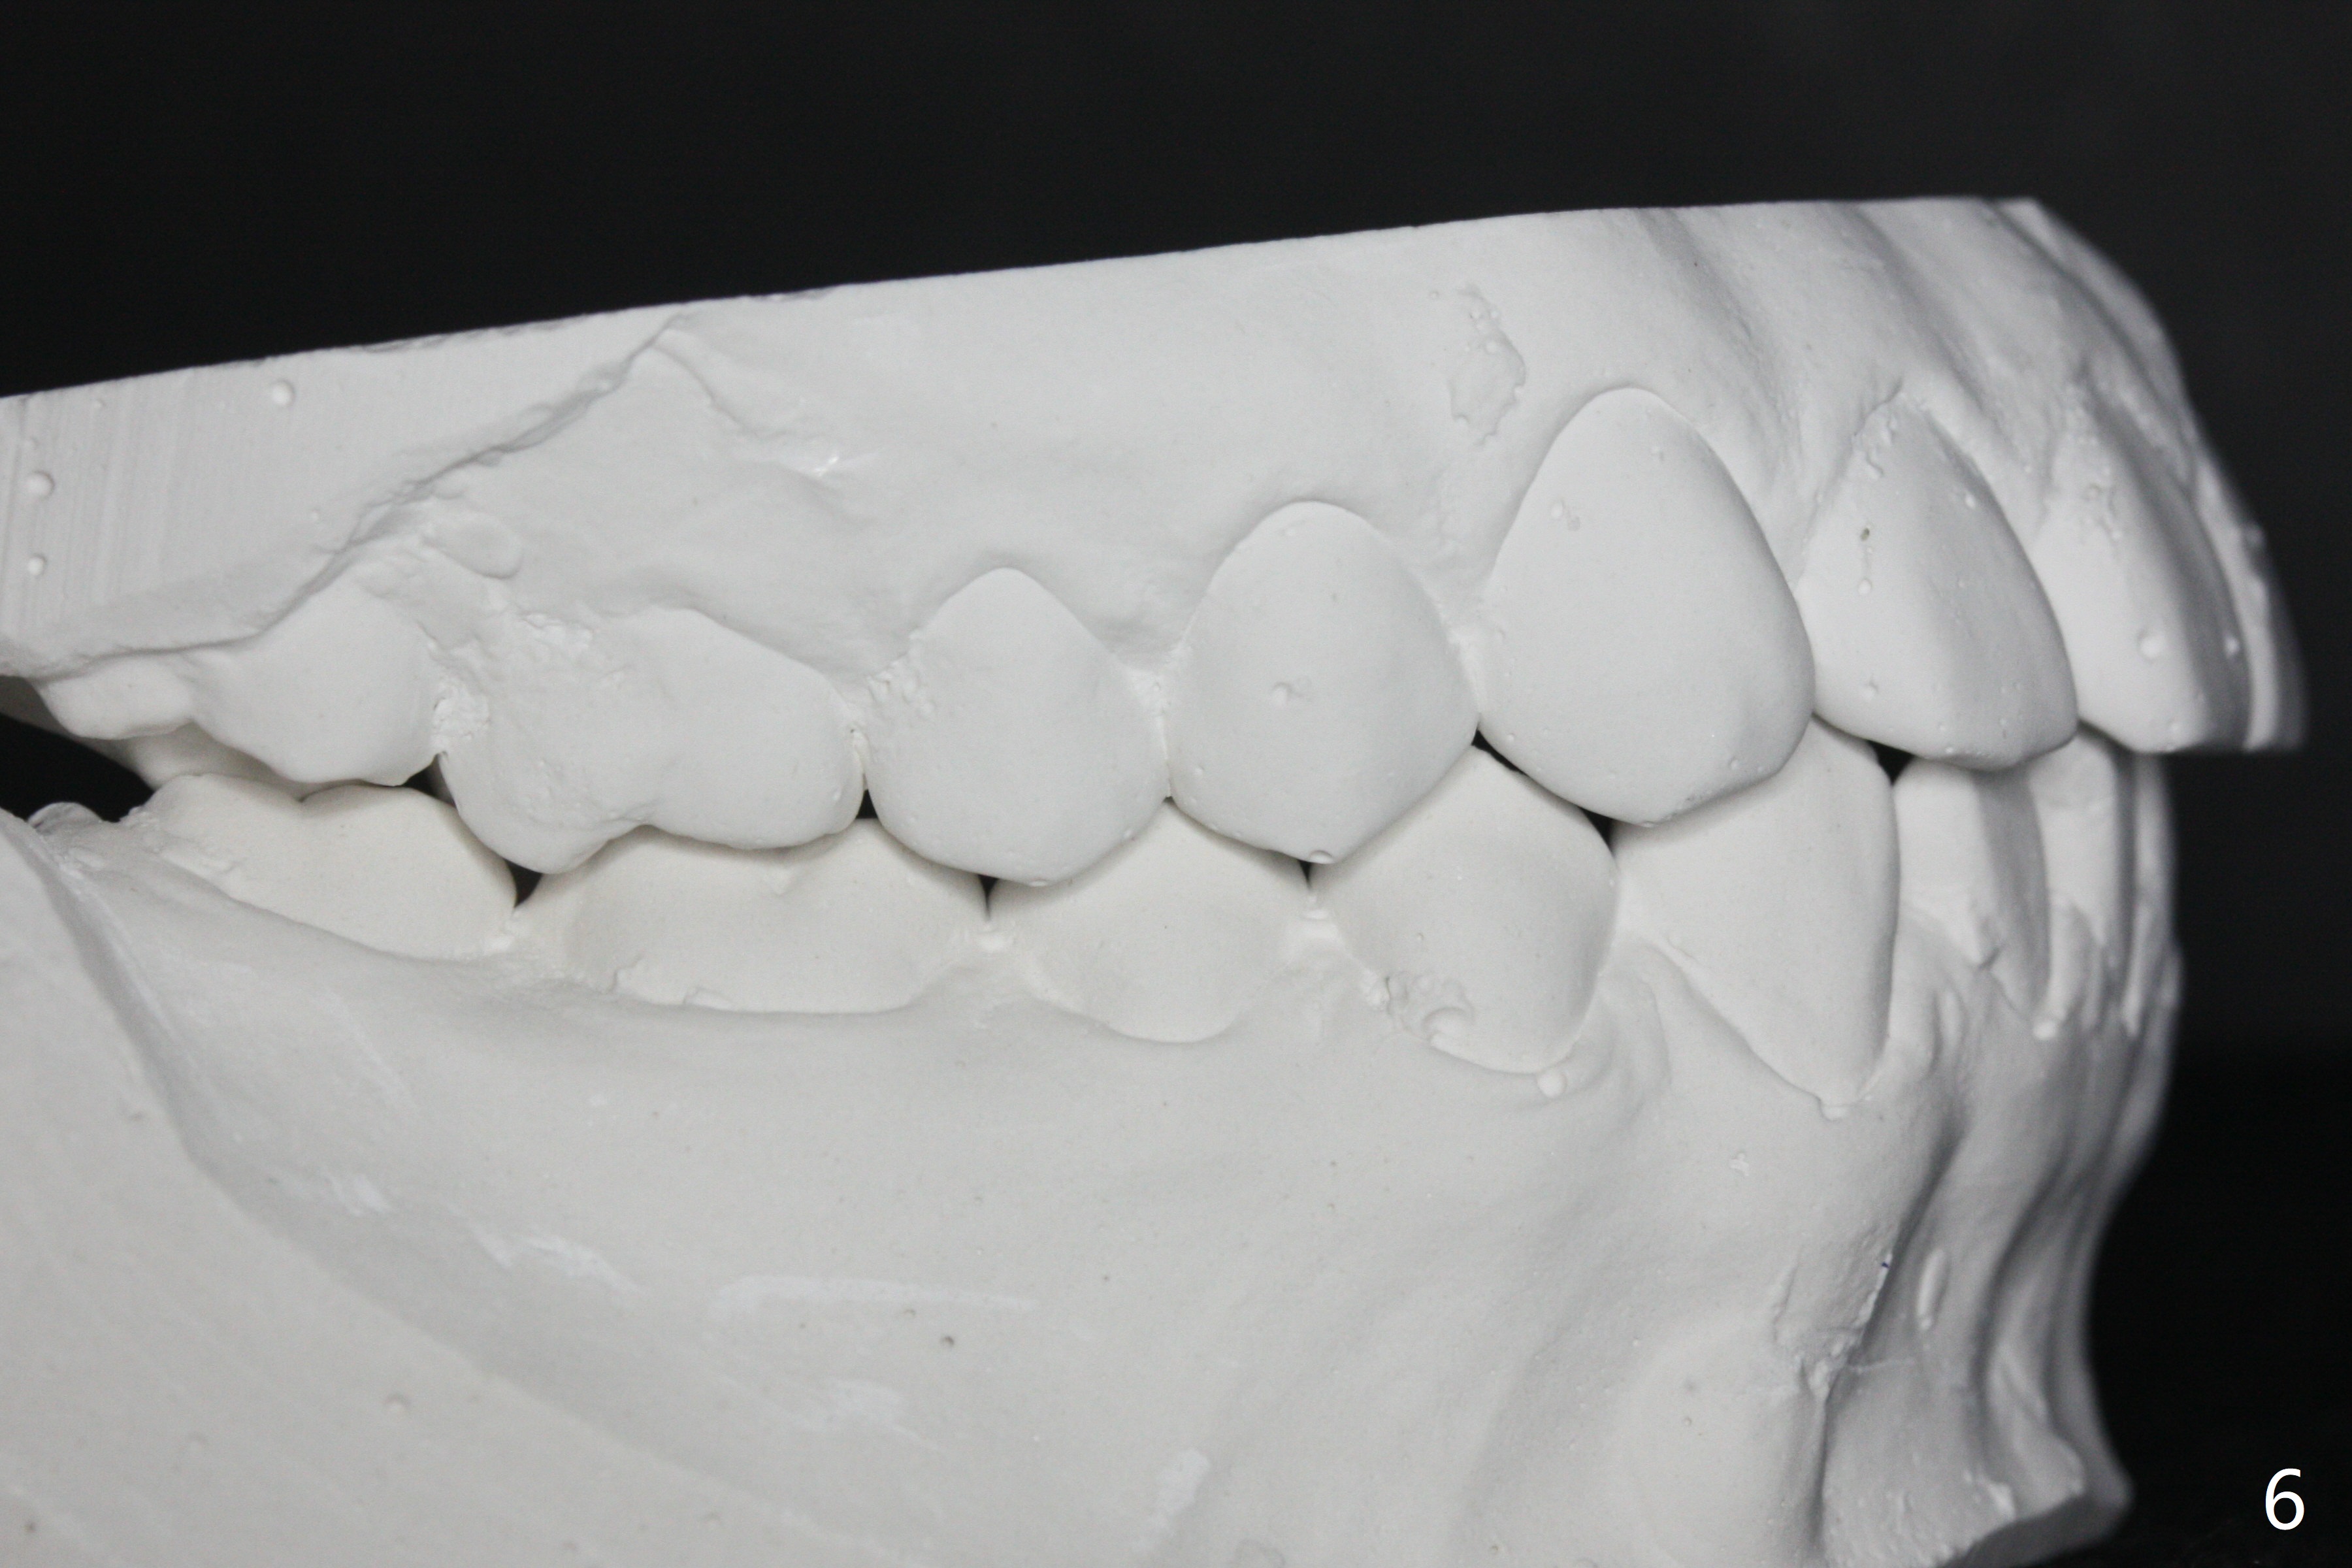

| Pre-op (11 y/o) | Post-op (12 y/o) | Follow Up (14 y/o) |

A 11-year-old man starts orthodontic treatment and finishes in 9 months. Two years later crowding relapses because of loss of suck down retainers. It appears that lingual retainer is necessary.